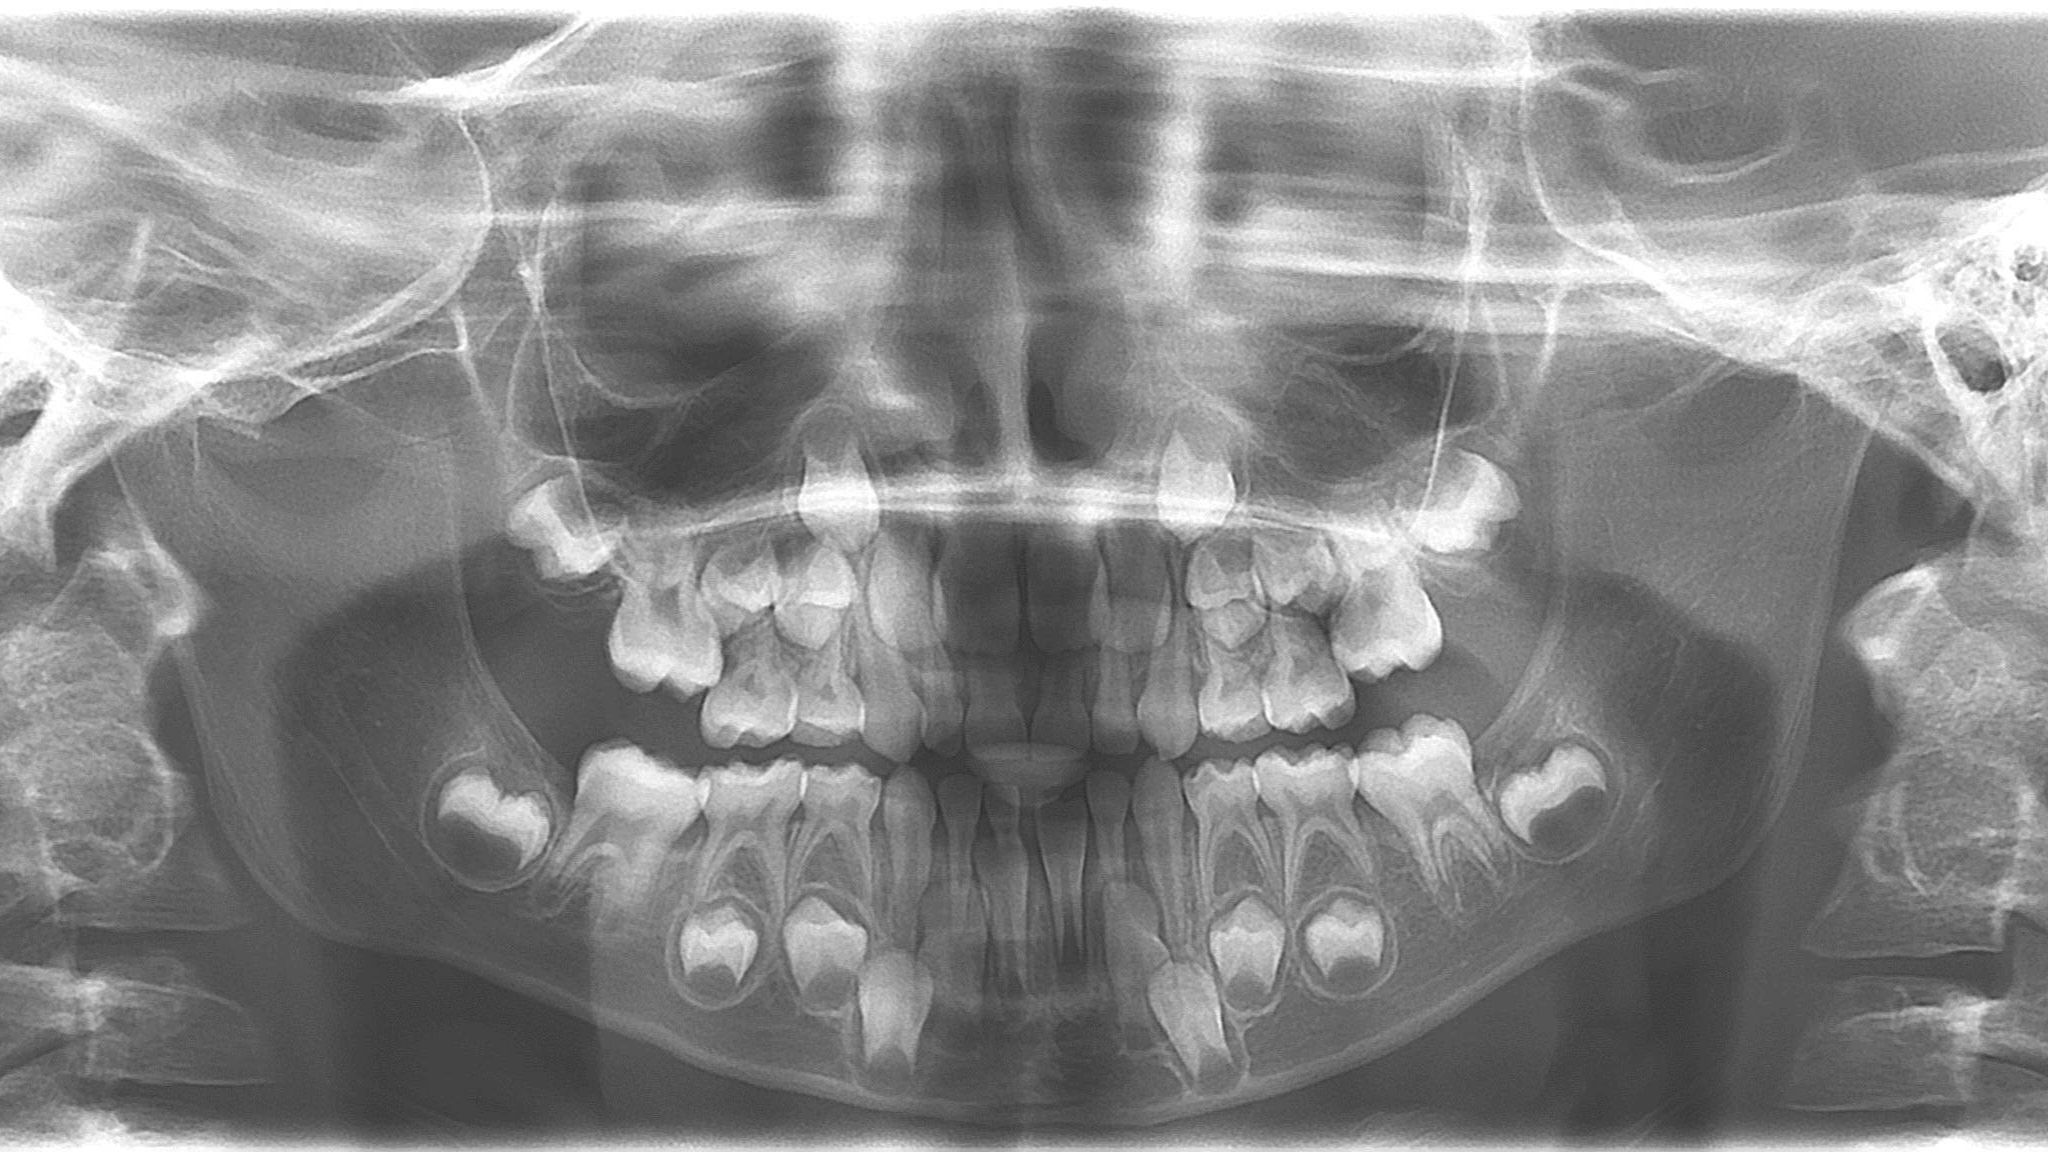

bilan des radiographies début et en cours de traitement